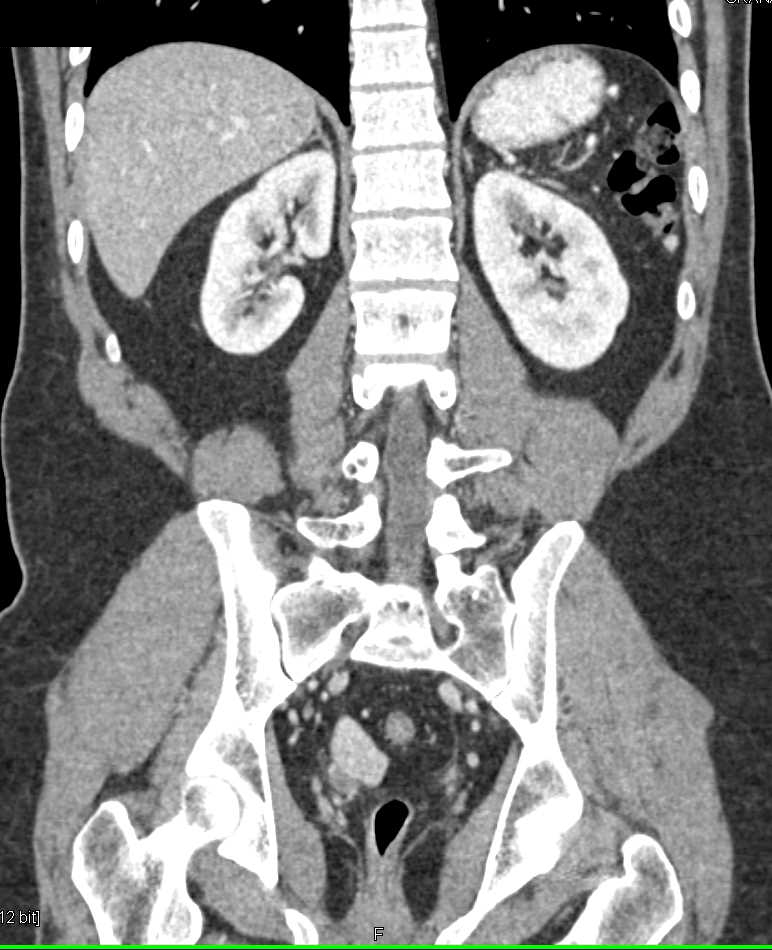

Testicular cancer and CT scans Chest X Ray Testicular Cancer Computed tomography (ct) scan ct scans can be used to help determine the. Testicular cancer treatment often involves surgery and chemotherapy. Which treatment options are best for you depends on the. Scrotal ultrasonography can confirm testicular origin. Testicular cancer, version 2.2020, nccn clinical practice guidelines in oncology in: These tests are done to determine if the suspected cancer has spread.. Chest X Ray Testicular Cancer.

From ctisus.com

Testicular Cancer with Low Density Adenopathy Genitourinary Case Chest X Ray Testicular Cancer If the cancer has spread to the lungs and is advanced, shortness of breath, chest pain, cough, or bloody sputum may develop. Testicular cancer treatment often involves surgery and chemotherapy. Which treatment options are best for you depends on the. Journal of the national comprehensive cancer network volume 17 issue 12 (2019) authors: Computed tomography (ct) scan ct scans can. Chest X Ray Testicular Cancer.

Clinical imaging findings. a CT imaging of the testicular tumor. b Chest X Ray Testicular Cancer Testicular cancer, version 2.2020, nccn clinical practice guidelines in oncology in: These tests are done to determine if the suspected cancer has spread. Computed tomography (ct) scan ct scans can be used to help determine the. Which treatment options are best for you depends on the. Over 90% of all tumors of the testes are primary germ cell tumors, and. Chest X Ray Testicular Cancer.